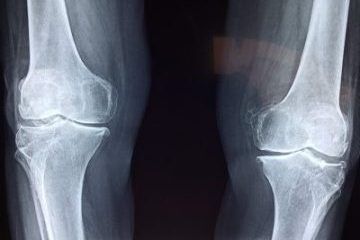

Darstellung der Ergebnisse einer Behandlung mit Phagentherapie bei einer osteoartikulären Infektion

Présentation des résultats d'un traitement par phagothérapie - infection ostéo articulaire